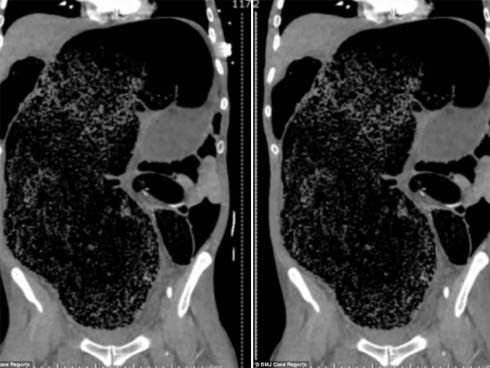

Táo bón 3 ngày không khỏi, người đàn ông khiến bác sĩ kinh hãi khi nhìn phim chụp đại tràng

Một bệnh nhân 57 tuổi tại Úc đã thoát chết khi bị 2 lít phân tích tụ trong cơ thể sau 3 ngày táo bón.